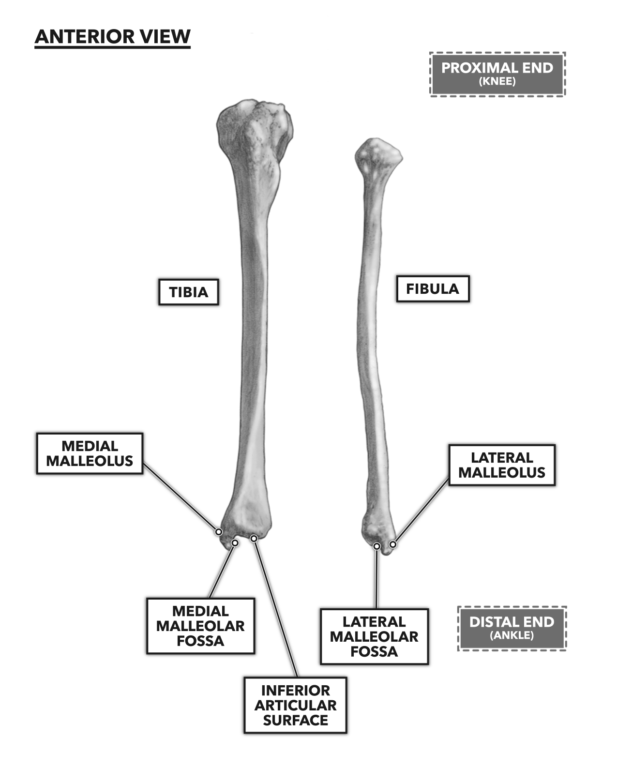

Tibia and Fibula Osteology of the Leg and Knee